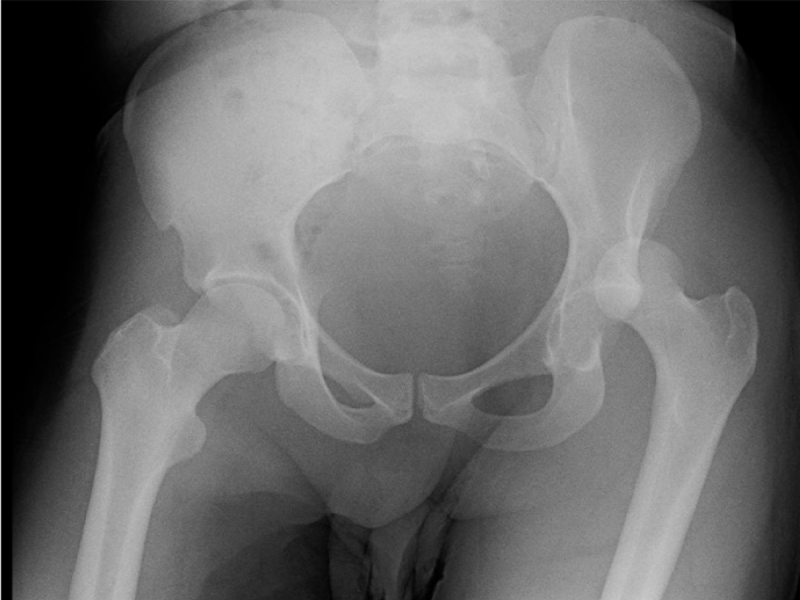

What's the Diagnosis? By Dr. Loran Hatch 20 yo male presents